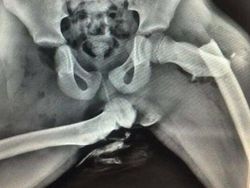

Mengapa Anda tidak boleh meletakkan kaki di dasbor mobil. Seorang wanita mengalami cedera mengerikan setelah meletakkan kakinya di dasbor mobil. Akibatnya, pinggulnya hancur. Foto: Boredpanda